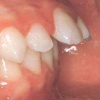

Ülemiste tsentraalsete lõikehammaste (intsisiivide) vahetumine. Retineerunud intsisiivid. Ülemised tsentraalsed esihambad lõikuvad orienteeruvalt 7-8-aastaselt. Enamasti lõikuvad samanimelised jäävhambad paaridena. Normaalne lõikumise järjekord 7, 5-aastselt: vt pilti